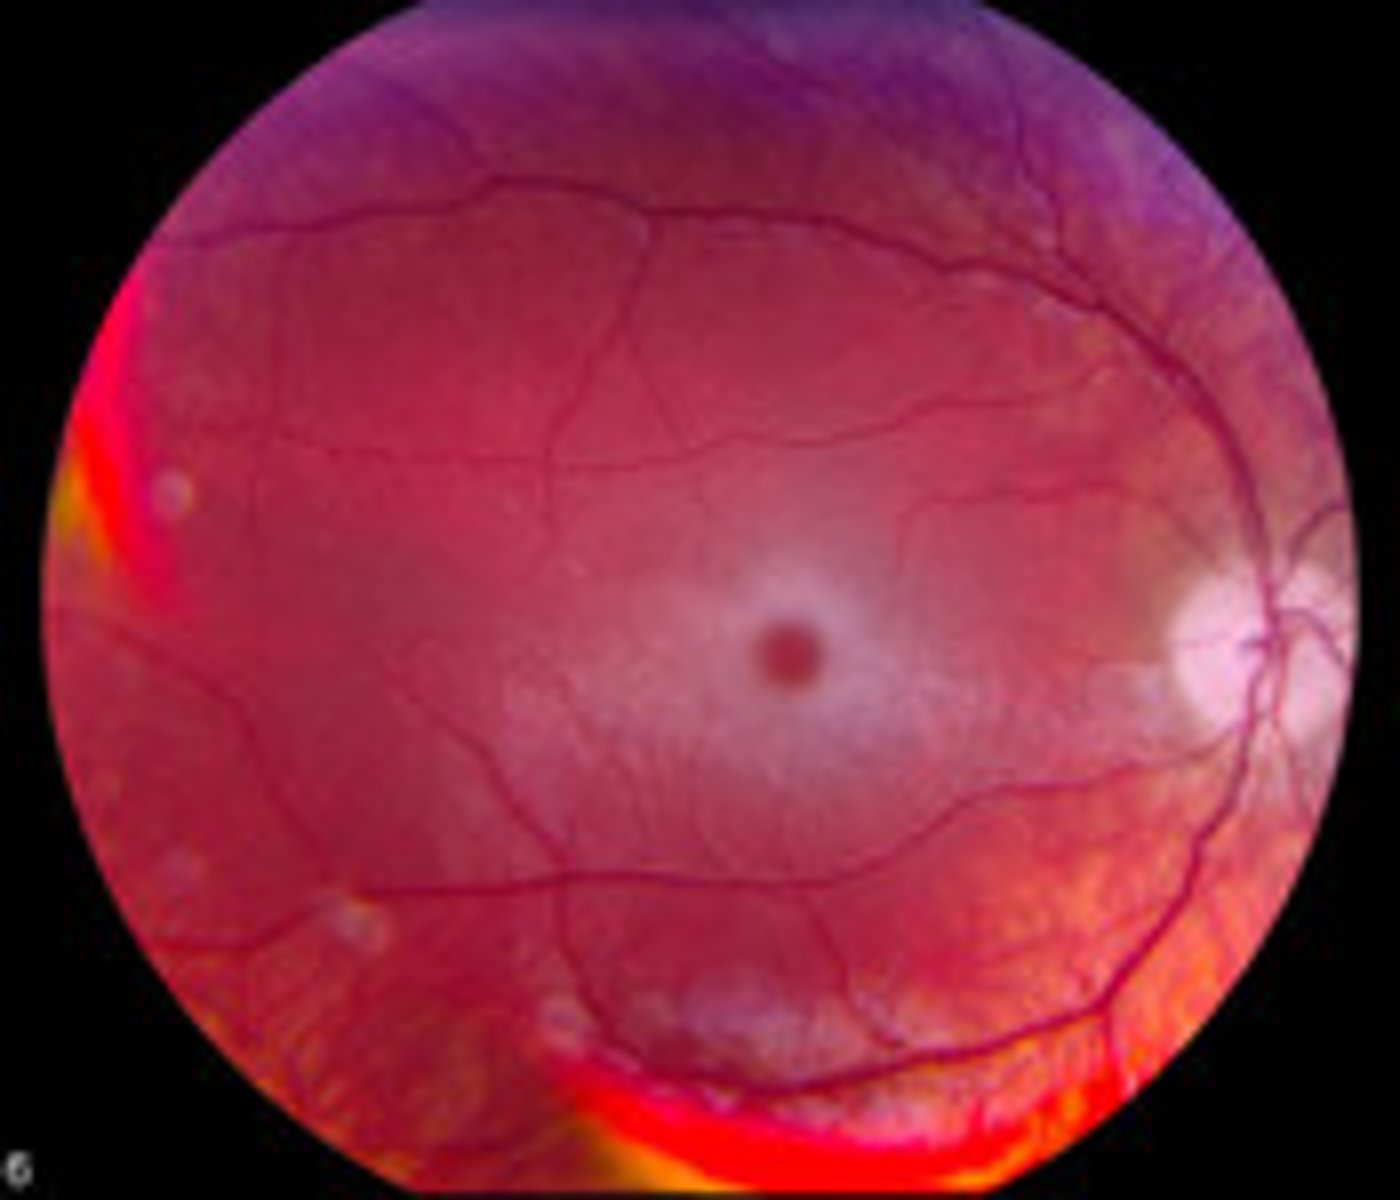

"Cherry-red spots" on macula

Tay-Sachs (ganglioside accumulation - NO hepatosplenomegaly)

Niemann-Pick (sphingomyelin accumulation w/ hepatosplenomegaly)

Central retinal artery occlusion

Retinal hemorrhages with pale centers

Roth spots (bacterial endocarditis)